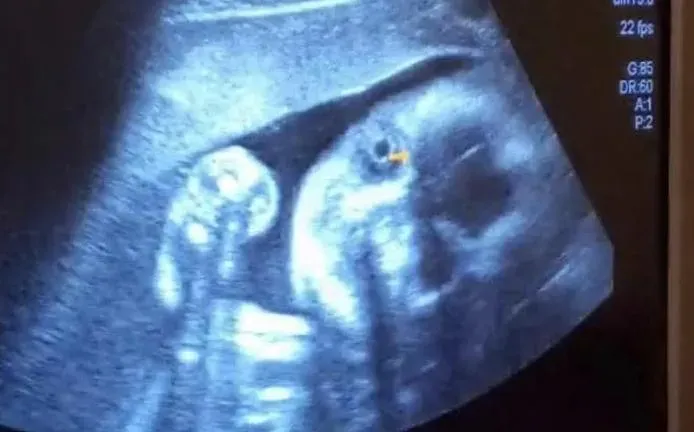

孕婦

子宮頸

超音波

超音波檢查

寶寶

蘇怡寧